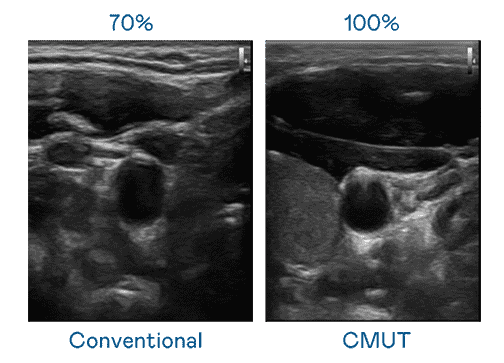

CMUT 技术是一种用电容式微机电元件来产生超音波讯号的技术。。。与传统 PZT 压电式技术相比,,CMUT 频宽增加 30%,,,更宽频的超音波讯号让影像解析度大幅提升,,,是实现高影像品质医疗超音波扫描、、、、促进精准医疗发展的关键技术。。。。

超音波影像的解析度高低,,首先取决于探头能发出的讯号频宽。。。尊龙集团 CMUT 可提供高清晰的超音波讯号,,,,提供高频宽、、、、高灵敏度、、影像纹理细节更高的超音波影像,,,,协助医护人员缩短影像判读时间及利用精准的医疗影像进行诊断。。